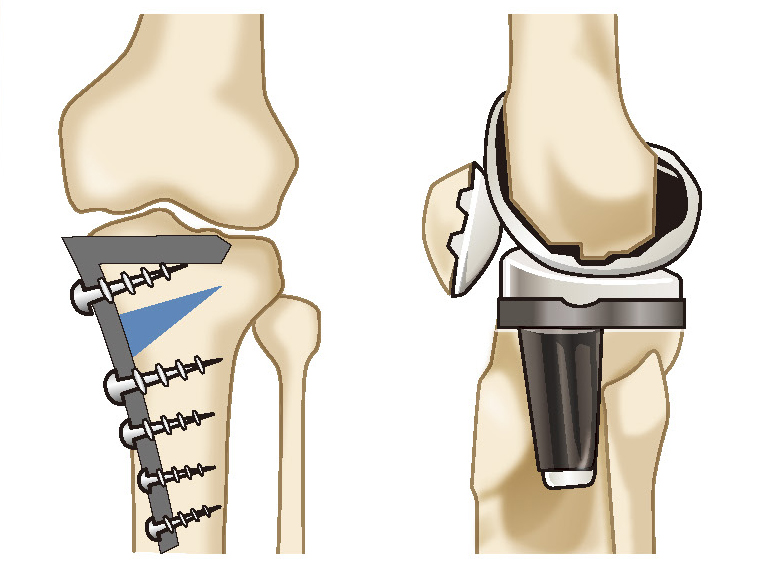

骨切り術と人工膝関節置換術

変形性膝関節症の手術には、大きく分けて、骨切り術と人工膝関節置換術という2つの方法があります。

骨切り術というのは、膝関節の変形している場所の骨を切って角度を矯正し、軟骨が残っている方に荷重軸を移動させることで、自分の関節を温存しつつ変形や痛みを改善します。

一方、人工膝関節置換術は、傷んでいる膝関節を人工の金属やポリエチレンに置き換えることで、早期に膝関節の変形や痛みの改善が期待できる手術です。人工膝関節置換術には、全置換術と部分置換術があります。

骨切り術

骨切り術は、軟骨のすり減りや変形が膝関節の内側だけ、もしくは外側だけに限局している場合に適応となります。特に多いのは、すり減りが内側に大きくO脚になっている人です。

骨切り術にはいくつか種類があり、これまで一般的に行われてきたのは、「高位脛骨骨切り術(HTO)」といって、脛骨(すねの骨)の上の方を切って角度を矯正する方法です。

最近は、より患者さんの状態に合わせた骨切り術が行われるようになってきました。例えば、脛骨の内側から外側に向かって骨を切り、内側を開いて矯正する「内側開大式高位脛骨骨切り術(OWHTO)」、脛骨と大腿骨(太ももの骨)の両方の骨切りを同時に行い、できる限り正常な状態へと改善する「ダブルレベルオステオトミー(DLO)」、膝蓋骨の位置を保つことで術後の軟骨損傷の発症リスクを減らす内側開大式脛骨粗面下骨切り術(DTO)などがあります。

…このように、新しい骨切り術の方式が開発されていることによって、これまでは、人工膝関節しか選択肢がなかった人が骨切り術で治療を受けられ、自分の膝を残しながら元の生活に戻ることも可能です。